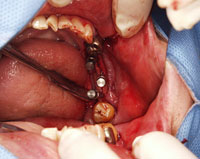

さて、では、このような骨が非常に薄く幅も少なく、骨の高さもない、という患者さまに対して当院の院長はどのようなインプラント手術を行っていくのか、ご説明してまいりましょう。

今回は直径4ミリ、長さ8.5ミリというとても短いインプラントを使用しました。インプラント手術後にレントゲンを撮影して神経ギリギリに入っているのが確認できています

1ミリの骨も無駄に削ることはできません。

削ったのは、最初の溝部分だけでした。骨を削らず(ドリリングせず)にインプラントを埋入する治療法です。

この写真は歯ぐきを開いて骨が見えているところです。

骨に縦に亀裂のようにみえるのが形成したところです。

円盤のような形をしている「ダイヤモンドディスク」という器具を使用します。

これはピザを切るときに使う道具に形が似ています。

骨はピザのように柔らかくはないのでエンジンを使用して切るのでスピードがあります。

数ミリでもずれたら骨が割れてしまいますので相当の技術を要します。

この写真は骨を圧し拡げる器具を入れているところです。

細いサイズから順番に使用していきます。

合計6本の大きさがあります。

非常に細かく時間のかかる作業です。慎重に慎重にゆっくりやらないと骨が折れてしまいます。

形は日曜大工などで使うネジに似ています。

サイズを順番に使っていき徐々に骨を圧縮しながら押しひろげインプラントが埋入できる緻密な骨を形成します。

薄い骨を割ることなく埋入できましたので人工骨を入れることもなく自分の固い骨がインプラントの周りにある状態で初期固定が安定したインプラントの埋入ができました。

初期固定とは、インプラントを埋入した時、インプラントをねじっても回らない状態のことです。細かった溝が拡がっているのが確認できます。